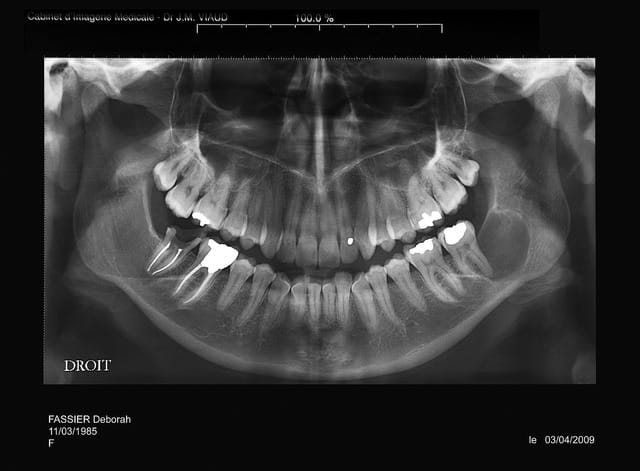

tu es sur que la 37 n'est pas en cause?

le problème c'est que je n'ai pas revu la patiente pendant 4 ans et que je ne sais pas l'etiologie exacte

je "subis" mon premier problème de dent de sagesse, si j'avais eu à traiter lors du 2° pano ça ne me faisait pas de soucis, mais là!

à priori 31/03/2006 pas si vieux que ça je croyais que c'etait 2004, donc évolution rapide